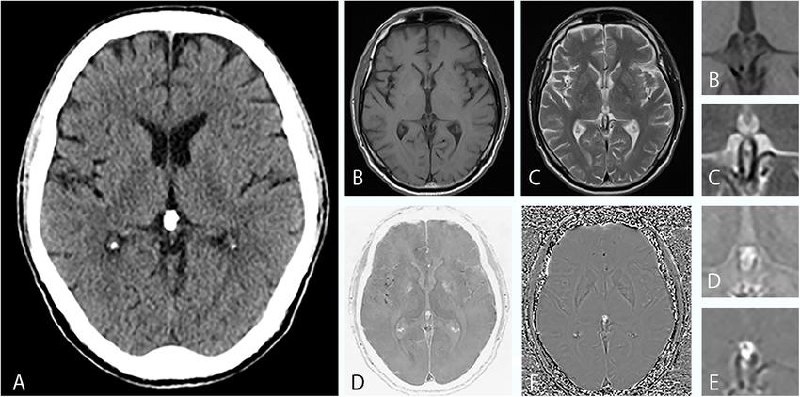

В эпифизе часто обнаруживаются кальциевые образования, известные как corpora arenacea («мозговой песок»).

— выявляются при визуализации и гистологических исследованиях,